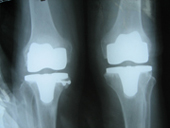

Arthritis both knees varus deformity pre op Post op Total Knee Replacement Post op Total Knee Replacement